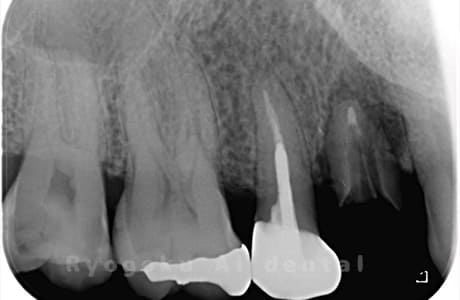

Case10

-

術前

術後

- 原因

- 左下6番欠損

- 治療内容

- インプラント治療

- 治療費用

- 約600,000円

左下の奥歯に歯を入れて欲しいとのことでご来院された患者様です。インプラント治療が最適とご提案させて頂き、治療を行いました。経過も良好で、大変満足して頂けました。

<リスク・副作用>

治療後、痛みや違和感、出血、腫れなどが出る事があります。喫煙者、糖尿病などの方の場合、歯が生着しない場合があります。